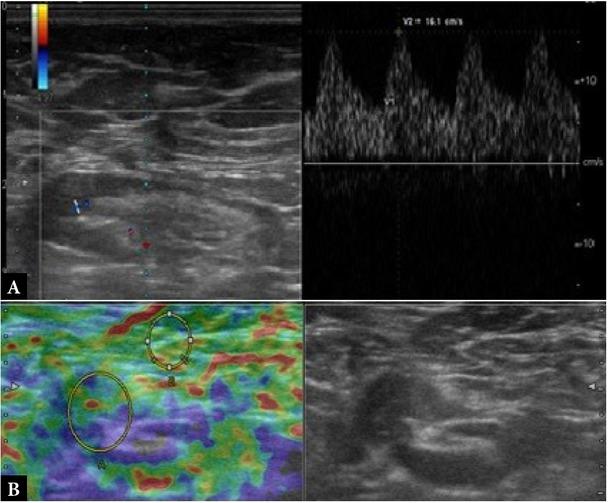

Fig. 2